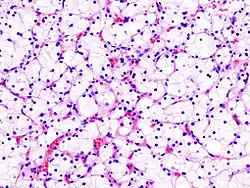

![]() Микрофотография, демонстрирующая наиболее частый тип рака почки — светлоклеточный (окраска гематоксилином и эозином) | |